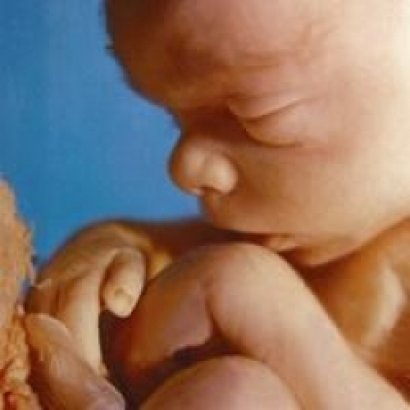

Плід на 21 тижні вагітності виріс приблизно до 20 -25 сантиметрів і важить 360 -400грамм. Його травна система все більше вдосконалюється, захоплюючи амніотичну рідину, малюк тренує свій стравохід і легені. На цьому терміні можна сформувати смакові пристрасті малюка.

21 тиждень вагітності, фото плода

Розмір плоду вже становить 18 см, а вага дитини досягає 350 грам. Матка подннімается над пупком приблизно на 1 см.

Дитина активно розвивається і росте, накопичуючи підшкірні жири. Малюк здатний здійснювати глотки, на його мові формуються смакові закінчення.

Лікарі на 21 тижні вагітності направлять вас на планове УЗД, де можна побачити, що очі дитини все ще приховані за століттями, а сам плід знаходиться в постійному русі.